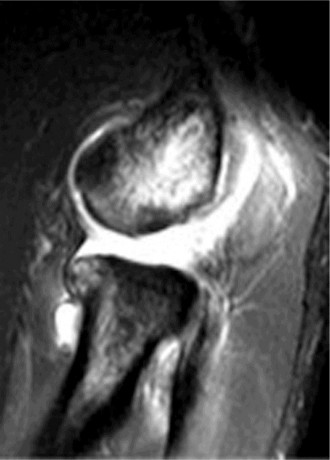

There is a positive lateral pivot shift of the elbow but does not open medially with isolated valgus stress. MRI is shown (Figs. 2–94 and 2–95).

Figure 2–94

Figure 2–95